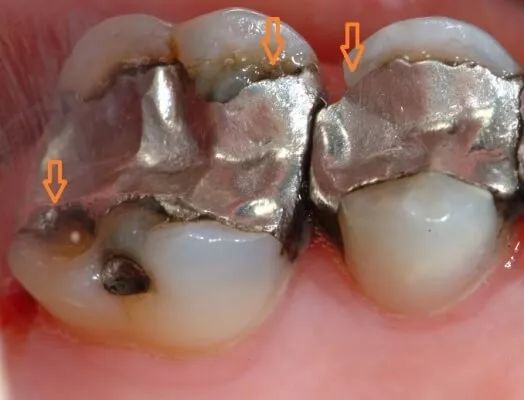

如果银汞合金已经损坏或者又有继发龋坏,这样是需要替换的。像这样的↓

如果银汞合金完好,也没有继发龋坏,功能上讲,是没必要替换的。如果是为了好看,那就需要自己权衡了。有一些国家已经禁用银汞合金,主要是汞污染环境和潜在的不安全因素。